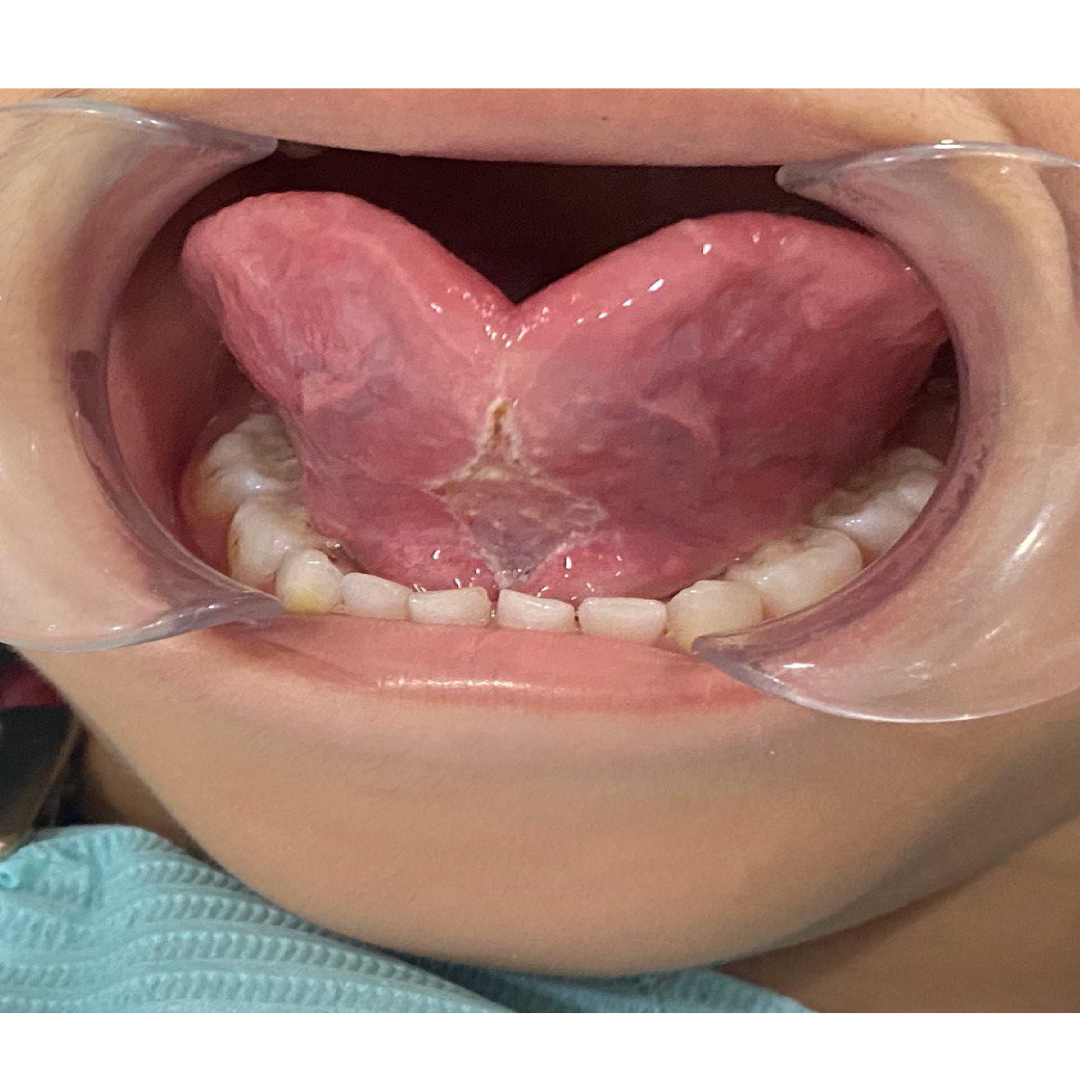

1. Tongue Tie (Ankyloglossia)

A tongue tie occurs when the tissue (lingual frenulum) under the tongue is too short or tight, restricting tongue movement.

📸 Before: Restricted tongue movement, speech/latch difficulty

📸 After: Freer tongue movement, improved function